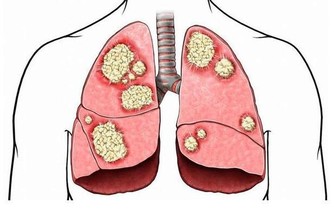

有人主張長期服用大劑量維生素C預防感冒和癌症,及降血脂等,但應嚴防過量中毒。

每日服用1克維生素C易發生腹瀉,一次服4克會導致尿酸尿,長期大劑量服用會使一些病人形成尿道草酸鹽結石,並使6—磷酸葡萄糖脫氫酶(G—6-- PD)缺乏症病人出現溶血。